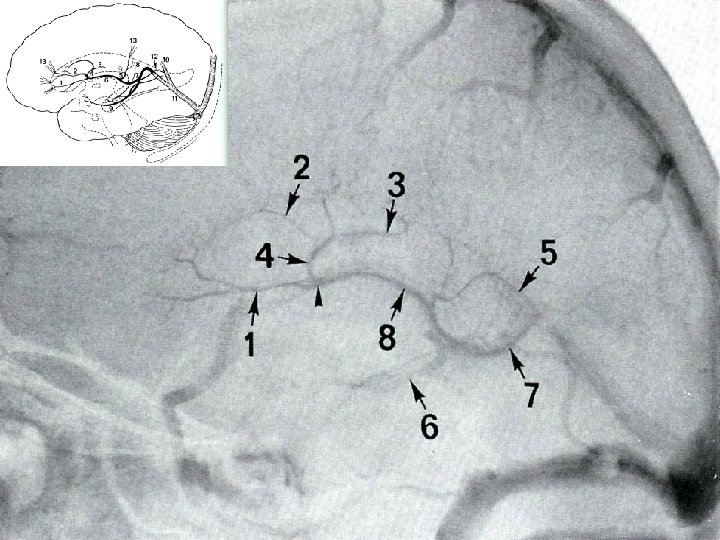

Deep Veins Thalamostriate vein Internal Cerebral vein (2) Vein of Galen Septal vein Basal vein of Rosenthal (2) Occipital vein (2) Posterior Pericallosal vein (2) Mesencephalic vein (2) Precentral Cerebellar vein (1) Inferior Sagittal Sinus Straight Sinus Michigan Neurosurgery

Deep Veins Michigan Neurosurgery